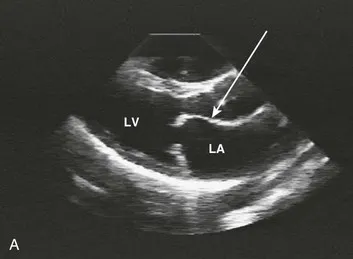

- Pathophys: Valve leaflets thicken and fuse → obstructs LV inflow → ↑LA pressure.

⭐ Ortner's Syndrome: Severe mitral stenosis can cause massive left atrial enlargement, which may compress the left recurrent laryngeal nerve, leading to hoarseness.